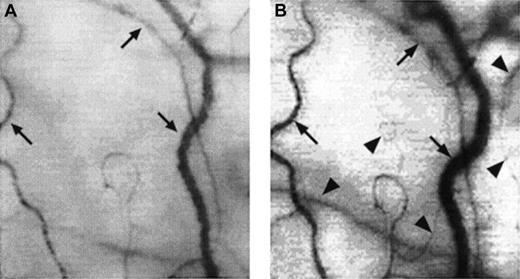

A typical view of the conjunctival microcirculation in an SCD patient 1 hour after hospitalization for painful crisis.

Optical magnification, × 4.5; onscreen magnification, × 125. Characteristic landmark features include extreme conjunctival avascularity, complete absence of capillaries, and a further decrease in the presence of arterioles and small venules, giving the bulbar conjunctival surface a more debilitating vascular presentation than the already avascular steady-state blanched appearance. Note the sustained and significant decrease in venular diameter, increased blood sludging caused by the stoppage of blood flow, a sustained and uniform vasocontraction, and the absence of focal occlusion or constriction in the vessels.

Acute and transient microvascular changes during painful crisis

There was a significant decrease in conjunctival vascularity during painful crisis, with a close to complete absence of capillaries and a significantly reduced presence of arterioles and small venules from the steady-state conditions (Figures3 and4A). In most cases, the disappearance of capillaries and small arterioles arose as a result of the absence of blood flow into these microvessels.

A few of the sludged large vessels did not show much change in diameter during crisis; however, most of the remaining large vessels showed an averaged decrease of 36.7% ± 5.2% in the diameter (compare Figures4A and 4B).

Conjunctival red cell velocity, which was measurable in 16 of 18 SCD patients during steady-state conditions (velocity groups 1 and 2 in Table 4), either slowed significantly (46.6% ± 13.1% decrease in red cell velocity from steady-state values; P < .01) or was reduced to a trickle (≤ 0.2 mm/s or unmeasurable) when quantified within 5 hours after hospitalization for crisis treatment.

These acute microvascular abnormalities were transient, and the microvasculature reverted to steady-state values after resolution of painful crisis (postcrisis). In reality, normal steady-state values are comparable to postcrisis values made 1 month after crisis resolution. During crisis resolution, reemergence of capillaries and arterioles (reperfusion) was observed in all patients (Figure 4B).